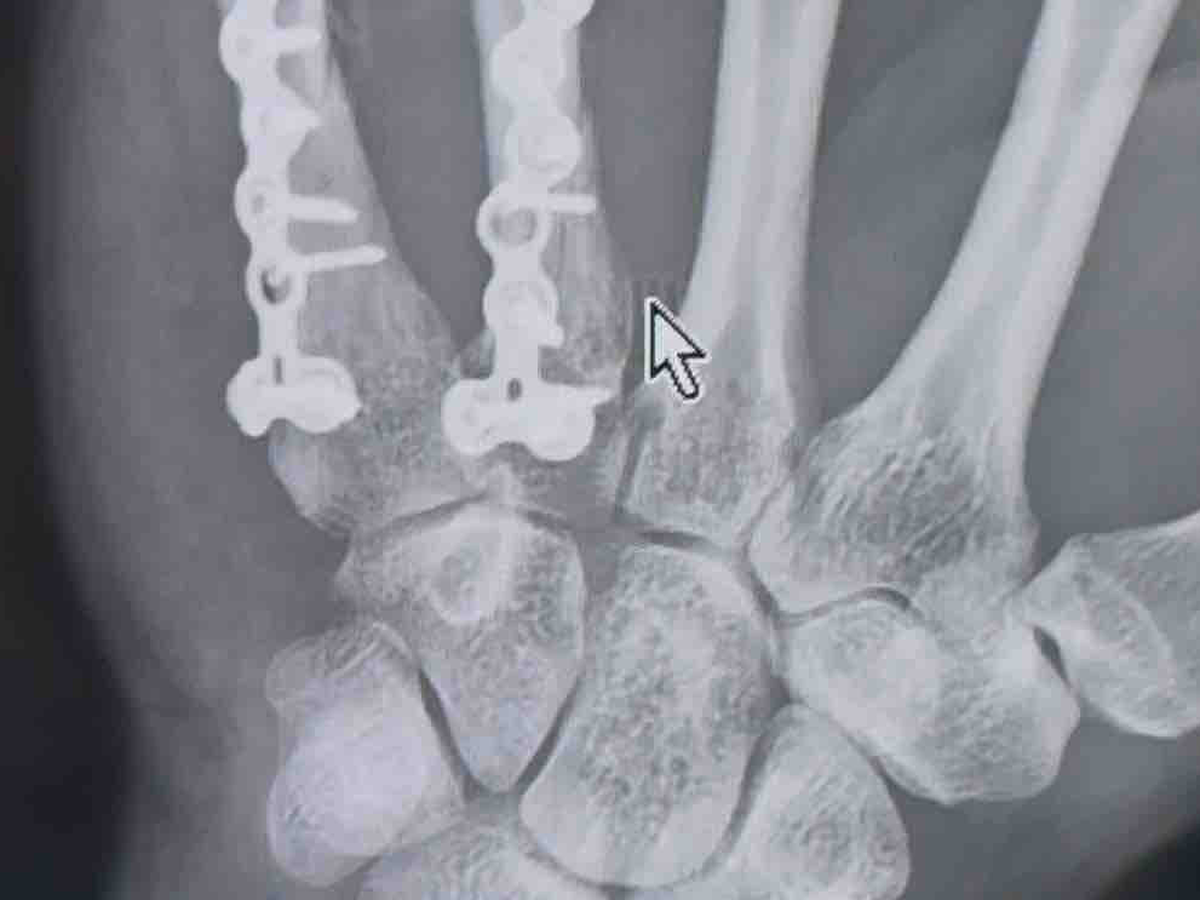

Our son, Ted Hemberger, recently suffered a traumatic injury — breaking his hand in three places. He’s now facing major surgery and a long road of physical therapy and recovery. Ted is currently living in Medellín, Colombia, without insurance or financial support, and the cost of treatment, medications, and living expenses is overwhelming.